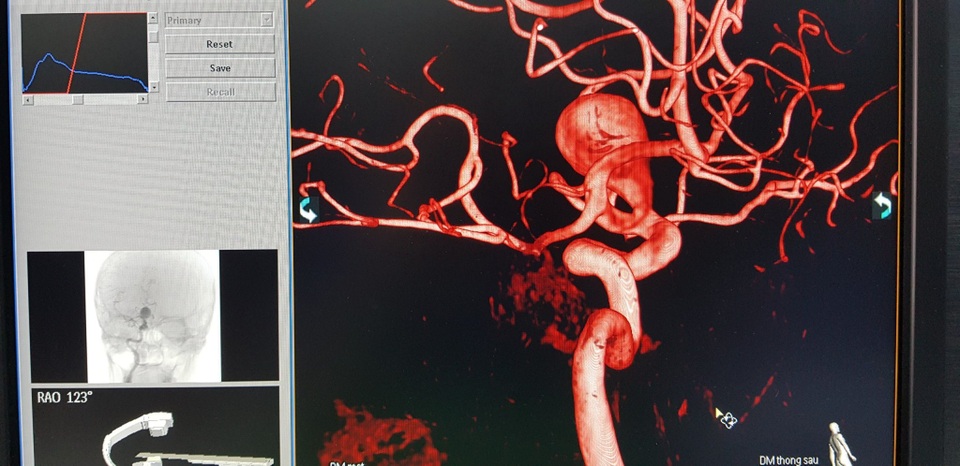

Kết quả chụp DSA phát hiện túi phình khổng lồ ở động mạch cảnh trong bên phải trong não bệnh nhân H. Đoạn động mạch mắt có kích thước 17 x 30mm và được xem là lớn nhất từ trước tới nay tại Bệnh viện Trung ương Huế và nếu túi phình vỡ thì tỉ lệ tử vong gần như tuyệt đối.

Túi phình khổng lồ động mạch cảnh trong phải